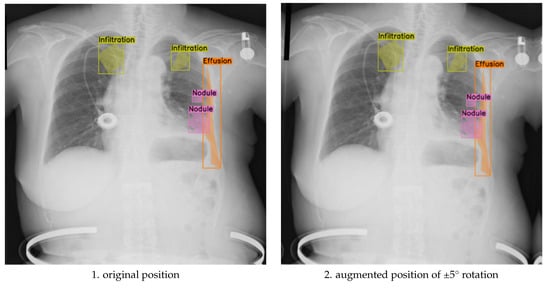

To assess the balance between anatomical label fidelity and augmentation effectiveness, we further analyzed the model’s performance under the ±5° rotation component, within a broader augmentation strategy that also included translation, scaling, brightness adjustment, and Gaussian noise. This mild geometric transformation preserved anatomical relationships while introducing sufficient spatial variability, leading to measurable improvements in segmentation quality. As shown in Figure 4, the augmented images maintain clear boundary alignment and anatomical realism, particularly in regions affected by multi-label pathologies. Compared to both the unaugmented baseline and the more extreme ±10° augmentation, the ±5° approach yielded smoother contours, improved lesion localization, and enhanced generalization across diverse patient presentations.

Figure 4.

Comparison of original and discrete rotations at (−5°, +5°) augmented chest X-ray images.

These results underscore the nuanced impact of augmentation magnitude: while ±10° rotations contribute broader positional diversity, they carry a higher risk of annotation drift. In contrast, ±5° rotations offer a controlled variability that strengthens the model’s sensitivity to subtle abnormalities without sacrificing spatial coherence. The optimal augmentation strategy depends on clinical priorities, robustness to extreme imaging conditions versus precision in fine-grained abnormality detection, and may benefit from a hybrid approach that combines both rotation levels in training.